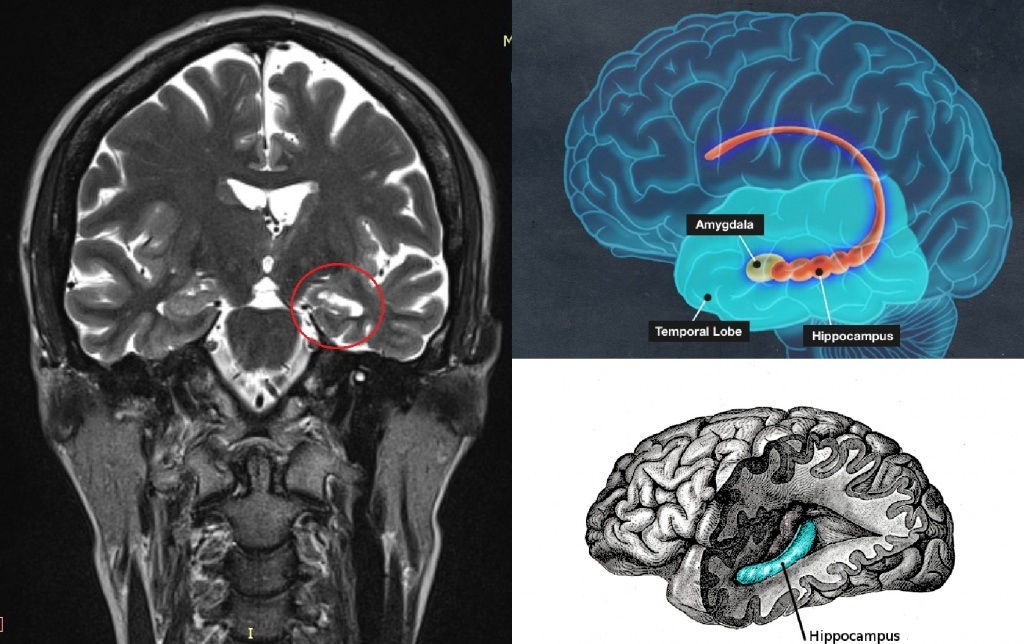

Где находится гиппокамп

Гиппокамп расположен в глубине височных долей мозга.

Название этой структуры происходит от греческого слова, означающего «морской конёк» — из-за характерной формы.

Гиппокамп — это небольшая, но критически важная структура в глубине височных долей мозга, по форме напоминающая морского конька. Он выполняет роль своеобразного «диспетчера» памяти, отвечая за превращение кратковременных впечатлений в долговременные воспоминания и помогая нам ориентироваться в пространстве. Благодаря гиппокампу мы можем формировать целостную картину событий, связывая факты, эмоции и детали окружения. Примечательно, что это одна из немногих областей мозга, способная создавать новые нейроны на протяжении всей жизни человека, что делает его ключевым звеном в процессе постоянного обучения и адаптации к миру.